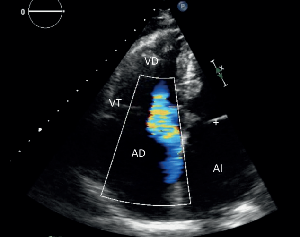

Minimanual Edocardioscopia para médicos de atención primaria

Actualmente, la ecografía transtorácica representa una herramienta diagnóstica valiosa y ampliamente disponible en la evaluación...